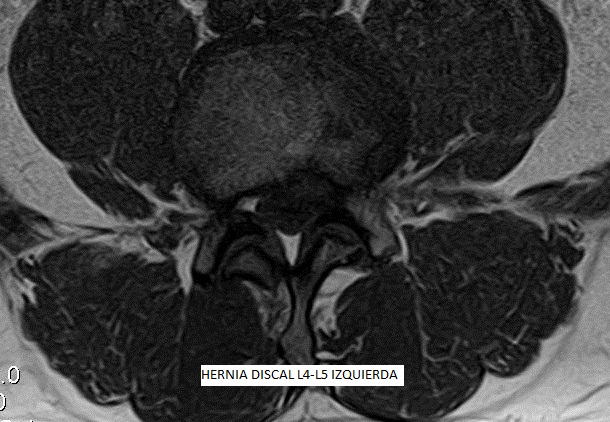

El mal d'esquena baixa o Dolor Lumbar, comunament té el seu origen en el funcionament incorrecte de diferents teixits de la regió lumbar incloent nervis, músculs, articulacions facetarias i discos intervertebrals. En la majoria dels casos, el dolor es produeix pel dany de diversos d'aquests teixits a la vegada, que funcionen com a peces d'un precís mecanisme on és necessària la integritat de cadascuna per a proporcionar una bona salut lumbar.

Les patologies del disc intervertebral es consideren de significativa contribució a la sensació dolorosa. Les hèrnies discals, protusions discals i l'artrosi, són les patologies degeneratives més comuns. La causa més freqüent de la Lumbàlgia o Dolor Lumbar és la degenerativa, associada a canvis biomecànics a la columna vertebral, resultant en un dany que pot arribar a severa intensitat i provocar una gran limitació de la nostra qualitat de vida.